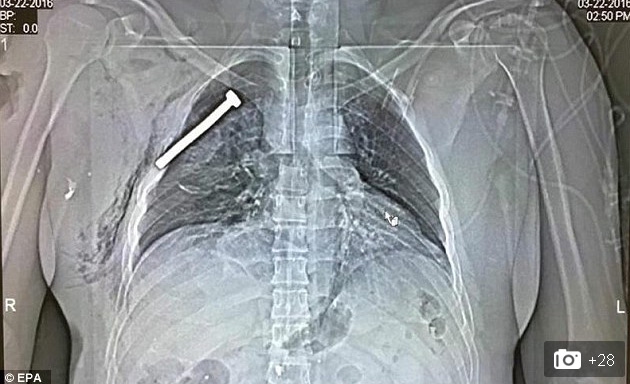

Bức ảnh X-quang gây sốc cho thấy chiếc đinh nhọn dài 7cm trong lồng ngực nạn nhân vụ đánh bom Brussel

Đây là bức ảnh chụp X-quang gây sốc vừa được báo chí phương Tây công bố, cho thấy một vật nhọn dài nằm cách trái tim của nạn nhân chỉ vài cm. Các báo cáo của cảnh sát Bỉ cho hay, có ít nhất một quả bom đặt tại sân bay Bỉ có chứa những vật nhọn và đinh sắt kiểu này. Khi bom phát nổ, các đinh nhọn này sẽ bắn ra xung quanh, cắm vào cơ thể nạn nhân và khiến cho mức độ sát thương tăng lên gấp nhiều lần.

Những đinh nhọn này có chiều dài rất khác nhau. Trong ảnh, vật nhọn dài tới hơn 7cm, găm thẳng vào ngực nạn nhân nhưng rất may là người này vẫn sống sót và đang được điều trị tích cực tại bệnh viện Quân đội vùng Neder-over-Heembeek thuộc phía Bắc thủ đô Brussels.